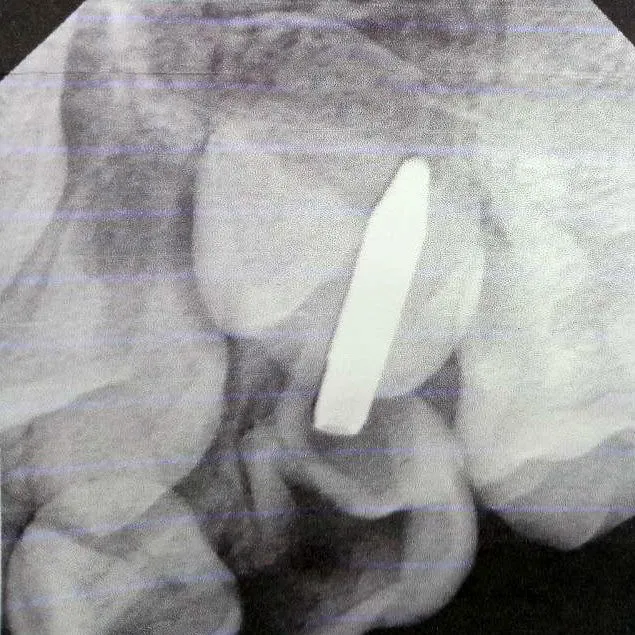

После осмотра и рентгеновского исследования врачи решили удалить поврежденный молочный зуб и извлечь инородный предмет через отверстие зуба.